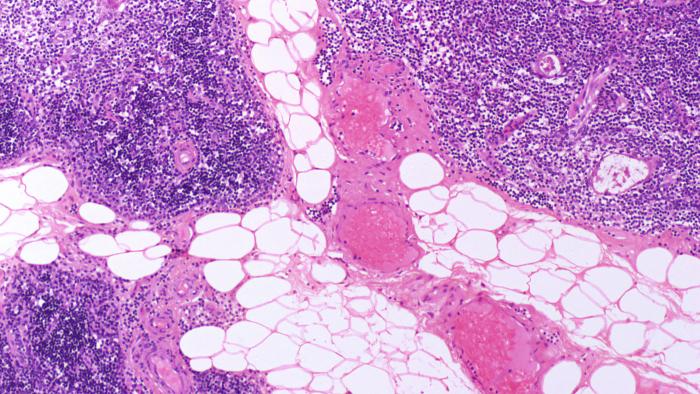

Existeixen altres serveis o institucions on els residents poden fer rotacions voluntàries si així ho desitgen, entre les quals destaquen anatomia patològica, immunologia, àrees d’investigació del Vall d’Hebron Institut de Recerca (VHIR) o la unitat de cures intensives.